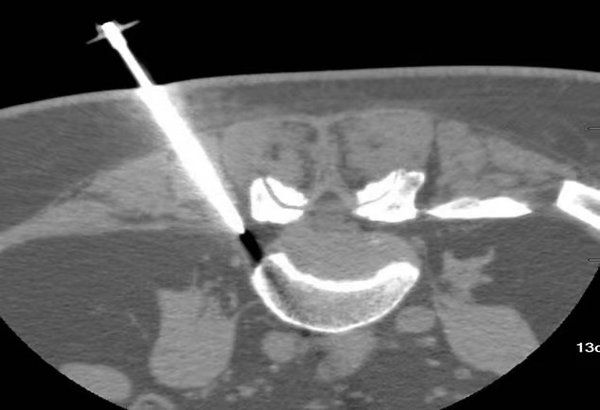

55岁的李女士,因反复腰疼伴左下肢疼痛麻木多年,经多次保守治疗无效,来到我院骨外科四病区就诊。腰椎MRI显示:L5-S1椎间盘突出。刘洋主任在与其家属充分沟通后,行CT引导下选择性腰神经根阻滞术。经CT引导下选择性腰、骶神经根阻滞术是治疗腰间盘突出症微创显著疗法之一。术后患者左下肢疼痛麻木的症状消失,第二天,原本被迫弯腰走路的患者,可以直起腰正常行走,现已痊愈出院。(供稿、摄像:CT诊断科 张天宇 编辑:宣传科 张宁)

CT引导下选择性腰神经根阻滞术